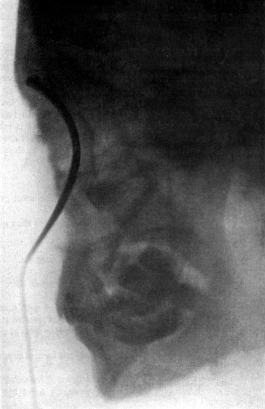

| 254. | Skiagram showing a Tumour of the Larynx | 476 |